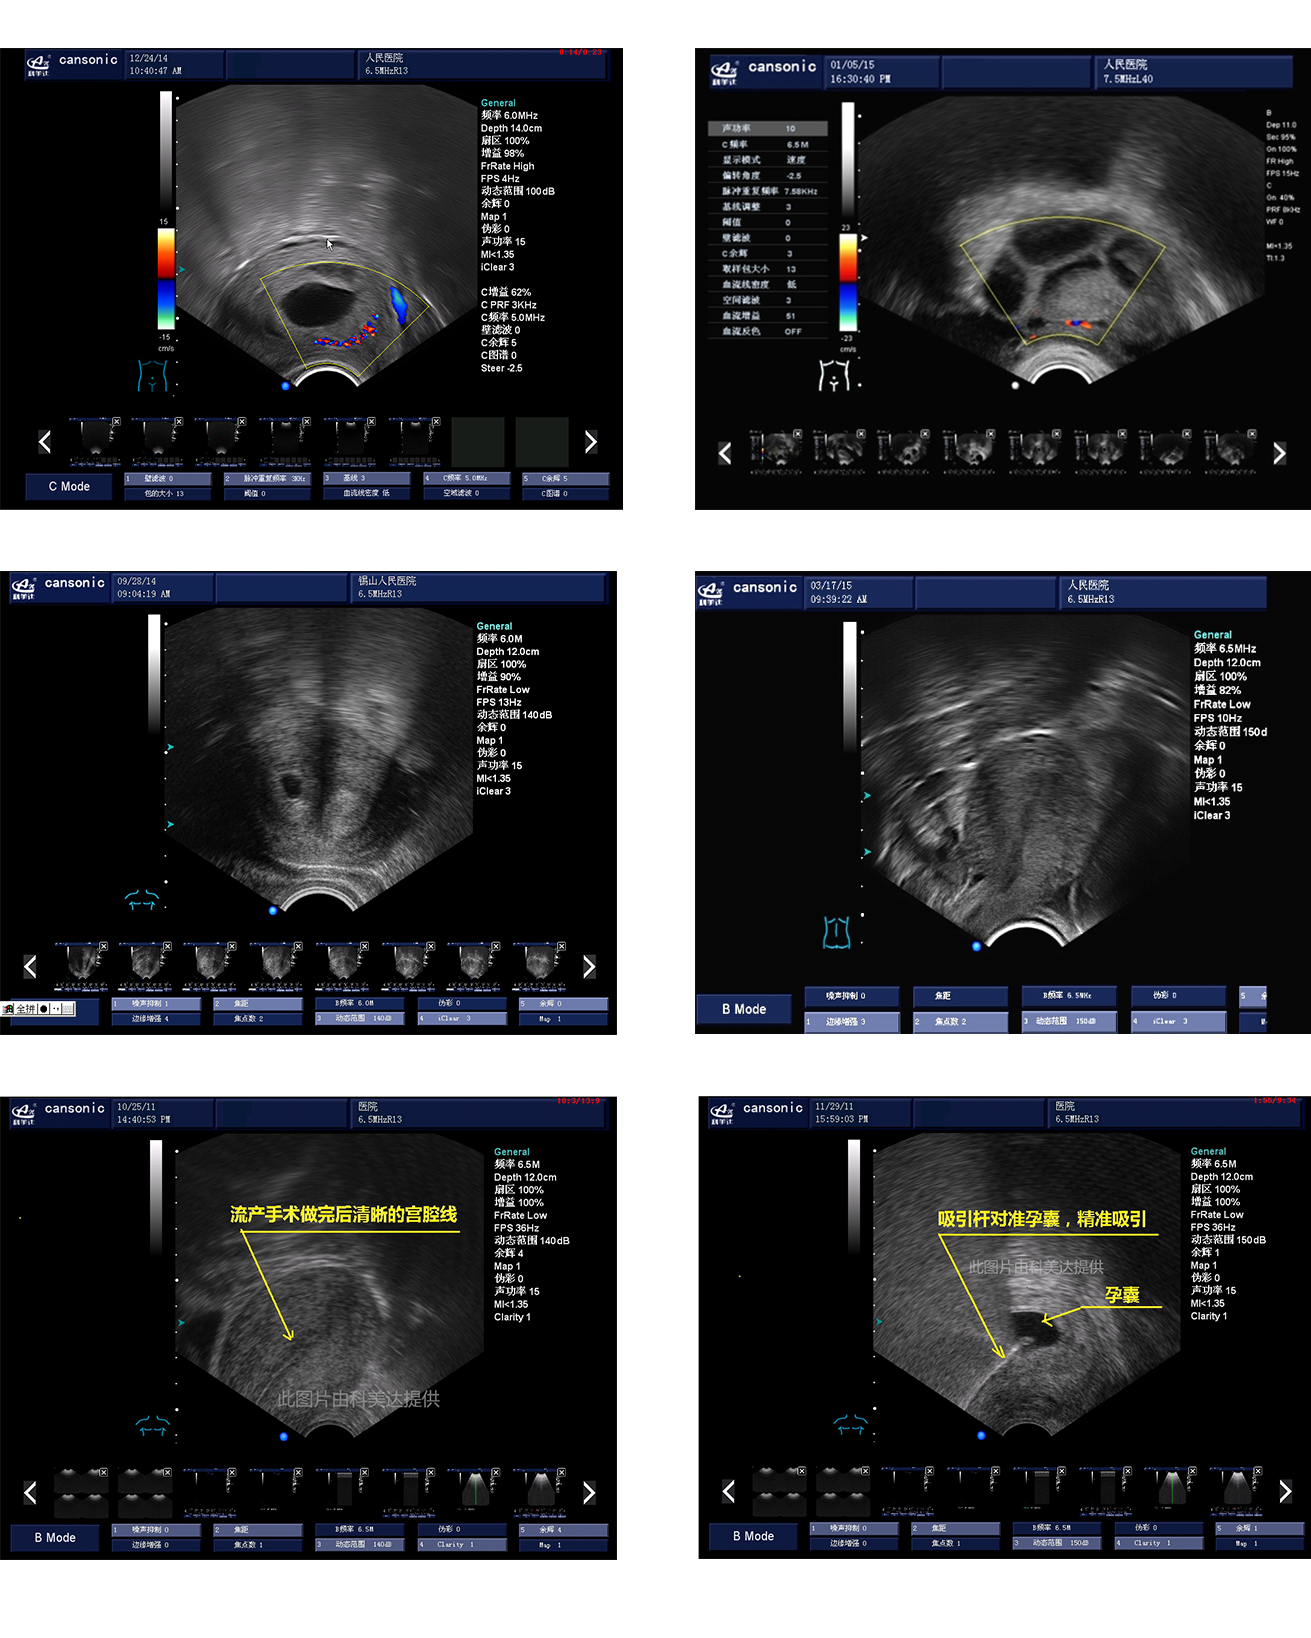

臨床圖示

1、薈萃前沿彩超技術(shù),使得超聲監(jiān)測與手術(shù)操作完美融合,實現(xiàn)宮腔手術(shù)的全程監(jiān)測

2、復(fù)合成像技術(shù),增強組織回聲,減少回聲失落,得到清晰、真實的手術(shù)影像

3、血流靈敏度高,清晰可見